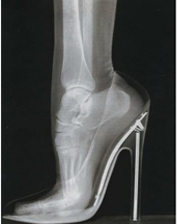

Your bones are some of the strongest tissues in your body. If an impact or a force is stronger than the strength of the bone on which it is acting, then a fracture may result. The most common causes of fracture are falls, motor vehicle accidents, and a weakening of the bone called osteoporosis.

» Participation in sports

» Wearing protective equipment when participating in sports

» Wear properly fitting shoes that provide shock absorption and stability